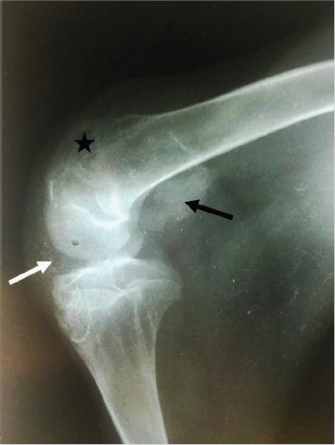

Radiographically, the stifle areas of the affected goats showed ventrocaudal PL in three cases (Figs. 2 and 3) and dorsal PL in the other two cases, for which surgical treatment was performed (Fig. 4A).

Fig. 2. Mediolateral radiograph of the right stifle of a 12-month-old goat with a unilateral PL. The radiograph shows a severely ventrocaudally luxated patella (black arrow) with loss of trabecular pattern of the distal extremity of femur (star), probably due to trochlear ridge hypoplasia. The infra-patellar fat bad is superimposed by a joint fluid due to stifle joint effusion (white arrow).